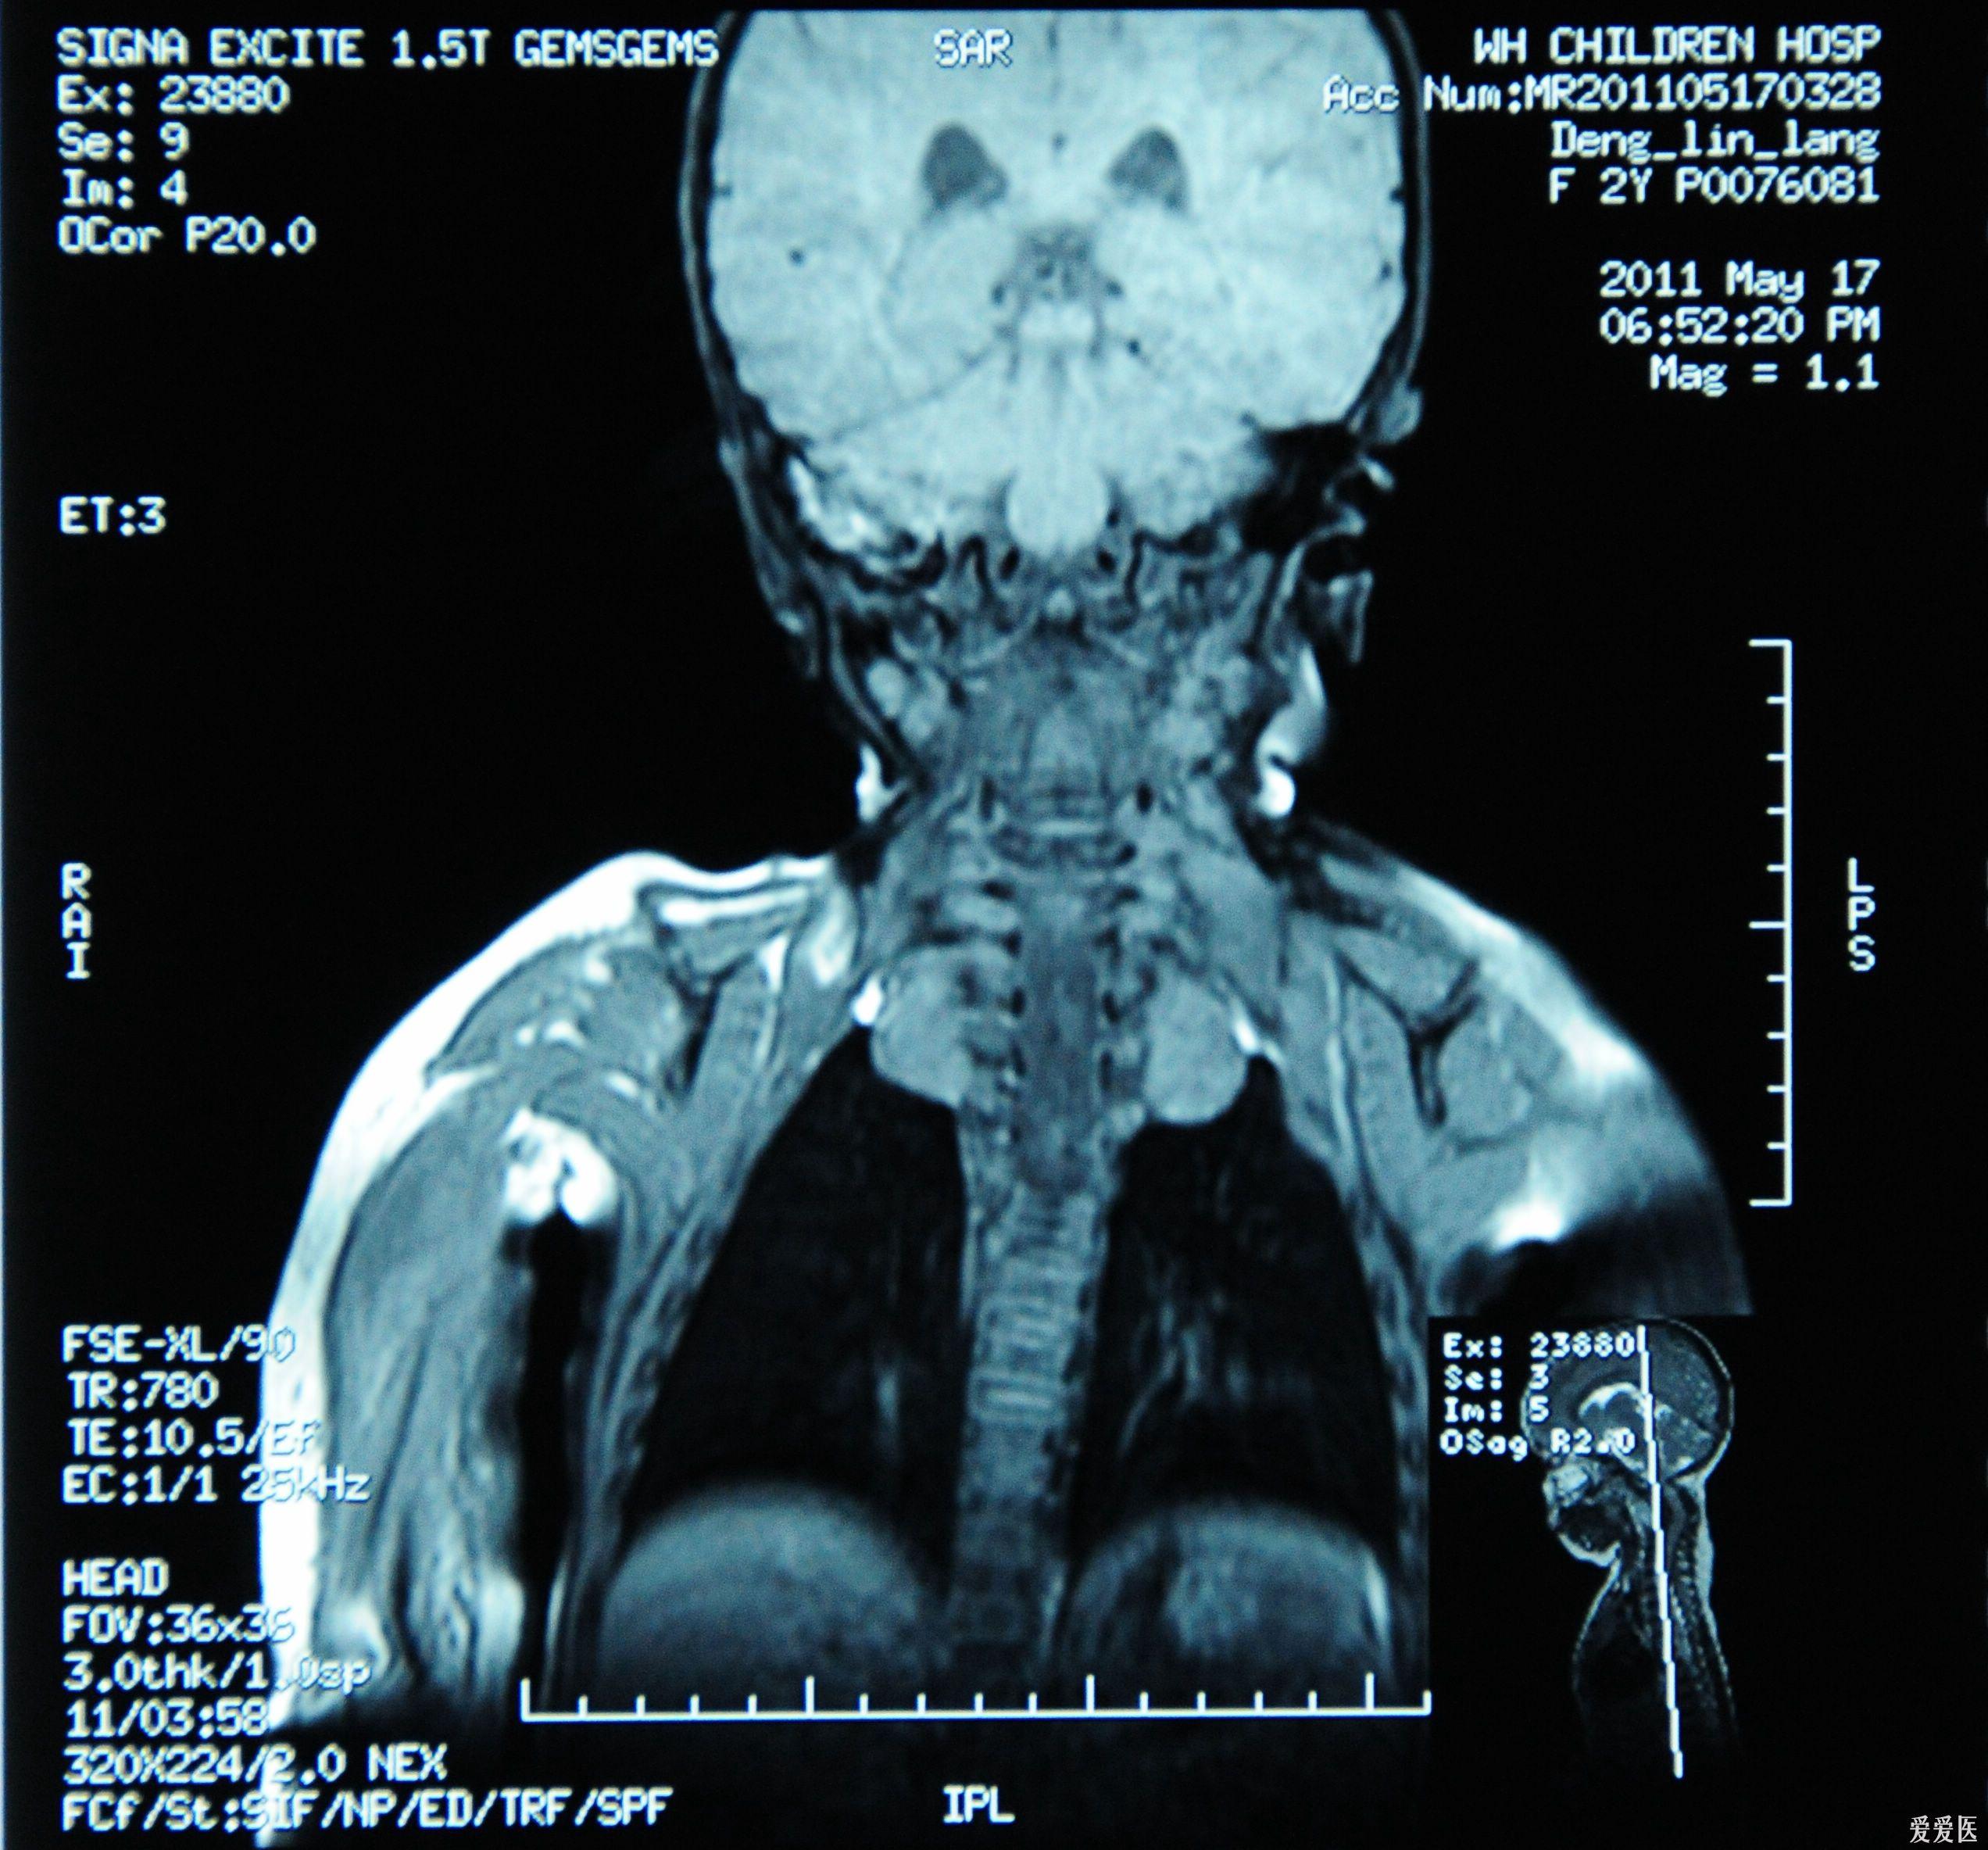

您好,您正在谈论磁共振中的长t1长t2信号. 这种信号变化可以在多种疾病中看到. 首先,它取决于信号的哪一部分. 出现此异常信号. 如果出现在头部,则可能是囊肿变性和坏死引起的. 因此,您所说的磁共振信号可能代表多种疾病,因此您需要根据信号的具体情况进行分析和判断.

你好!在MRI中,长T1和长T2信号阴影通常是接近水的信号,因此应考虑局部水肿或囊性变化. MRI对软组织具有出色的分辨率. 软组织检查比CT好肿瘤信号是长t1长t2,祝您健康. 如果您什么都不懂,可以问我.